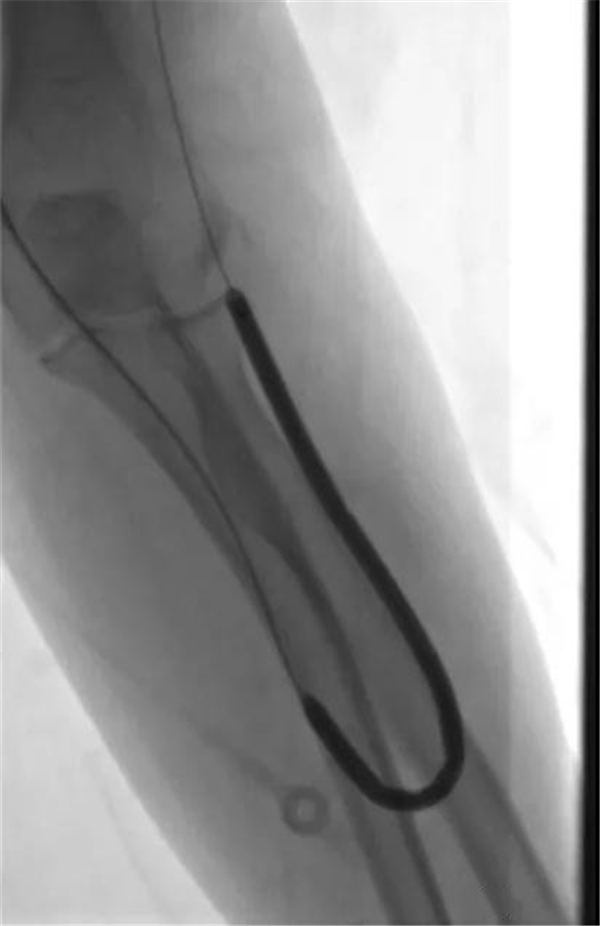

球囊完全扩张后,血管完全通畅,如下图。